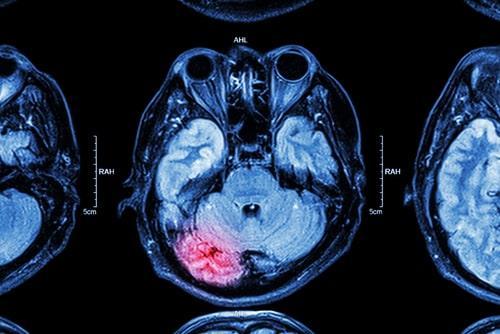

According to the Centers for Disease Control and Prevention, car accidents are the second leading cause of traumatic brain injury (TBI) hospitalizations, accounting for about 20 percent of these serious injuries. The force of a collision makes concussions and other brain injuries unfortunately common, and the effects can be long-lasting or even permanent. If you or a loved one has suffered a TBI in a car crash, an attorney can help you make the case for all possible compensation.

A TBI is an injury to the brain that results from a forceful blow to the head. The best-known example of a traumatic brain injury is a concussion, but depending on the force of the impact, TBIs can be much more serious. For a brain injury to be considered traumatic, it must affect regular brain functions in the short or long term, or both.